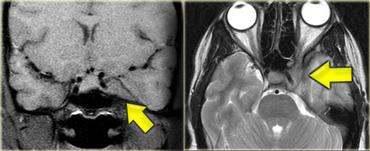

Trường hợp bên trái minh họa giá trị của Gadolinium trong việc phát hiện khối u.

Đây là bệnh nhân mắc Bệnh u xơ thần kinh loại II (Neurofibromatosis II).

Sau khi tiêm thuốc tương phản, hai u màng não và một u bao thần kinh được nhìn thấy rõ ràng.

Di căn màng não mềm thường không được phát hiện nếu không tiêm thuốc tương phản từ đường tĩnh mạch.

Trường hợp bên trái minh họa hình ảnh ngấm thuốc bất thường dọc theo thân não, dọc theo các nếp cuộn tiểu não (mũi tên vàng) và dọc theo dây thần kinh sọ số V trong hộp sọ (mũi tên xanh) ở bệnh nhân di căn màng não mềm.